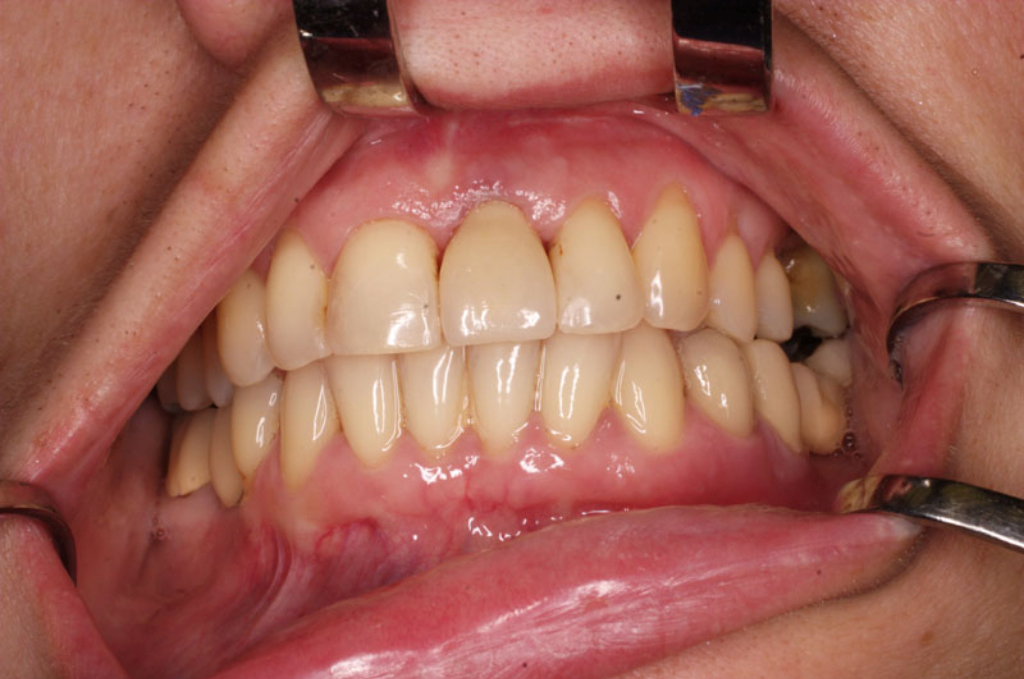

S těmito typy náhrad můžeme dosáhnout perfektní funkci, výbornou estetiku, fonetiku a současně zajistit u pacienta možnost dobré hygienickou péče a čištění, která je pro životnost implantátů velice důležitá.

Implantáty jsou osvědčeným a vyzkoušeným řešením, které dnes umožňuje zhotovení estetické a funkční náhrady.

• Dokonalé obnovení funkce a estetiky